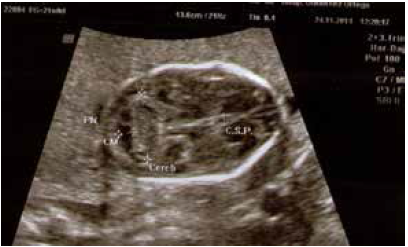

A las 19 semanas más 6 días acudió a valoración ecográfica de las 20 semanas, evidenciándose dilatación de ventrículos cerebrales, sobre todo a expensas de las astas anteriores, un tercer ventrículo dilatado y alto con cuerpo calloso pequeño y fino. La velocidad pico sistólica de la arteria cerebral media (VPS-ACM) era >1,5 MoM, compatible con anemia fetal grave, según las tablas de Mari.

En el resto de la exploración se evidenció edema subcutáneo generalizado, más acusado a nivel del cuello, donde el pliegue nucal medía 6,6 mm. También existía hidrotórax y ascitis con hepatomegalia (figuras 1,2 y 3).

En el estudio ecográfico de las 20 semanas se evidenció feto con una grave restricción del crecimiento intrauterino dada por una biometría fetal acorde a 16 semanas de gestación. Microcefalia significativa, un cuerpo calloso hipodesarrollado y refringencia periventricular aumentada a nivel de los ventrículos laterales, sin observarse calcificaciones parenquimatosas. Destacaba la presencia de atrofia cortical, con hipodesarrollo de las cisuras e hipoplasia cerebelosa. También, se visualizaba cardiomegalia tetracameral sin signos de anemia fetal (VPSACM: 1,4 MoM) y placentomegalia (56 mm). Había además aumento de refringencia intestinal y anhidramnios (figuras 4 y 5).

Ecográficamente se puede sospechar afectación fetal por CMV al evidenciar trastornos del crecimiento intrauterino, oligohidramnios, polihidramnios, hidropesía, calcificaciones intracraneales e intrahepáticas, hiperecogenicidad intestinal, microcefalia, ventriculomegalia, signos de hemorragia intracraneal y placentomegalia(5,6,7). Estos hallazgos solo están presentes en 15 a 52% de los fetos con infección fetal confirmada (8) y muchos de estos marcadores ecográficos estaban presentes en los casos presentados, lo que permitió orientar la sospecha diagnóstica.